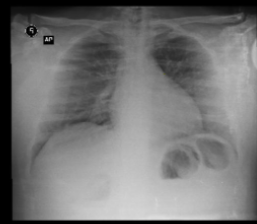

Demanda: Estudo de Caso Clínico (qual o meio de obte-lo: contrato NDA, orçamento?) das análises que fizemos (em anexo) de raio x e tomografia computadorizada obtidos em base pública realizado sob plataforma pública de deep learning com modelo abastecido por datasets públicos de pacientes suspeitos de contágio com covid-19 e outras doenças respiratórias****.

3 - Treinar o Modelo Mellieri Human de Rede Neural Convolucional para detectar o COVID-19 e outras doenças respiratórias em imagens de raios-X e tomografia computadorizada.

4 - Notamos que um paciente pode ter um misto de complicações respiratórias (Covid e Pneumonia por exemplo).

Qual impacto disto nas pesquisas e soluções para combate ao covid-19 como vacinas em função do estágio da doença a exemplo do metadados anexos já que os diagnósticos podem ser únicos para cada paciente no tempo?